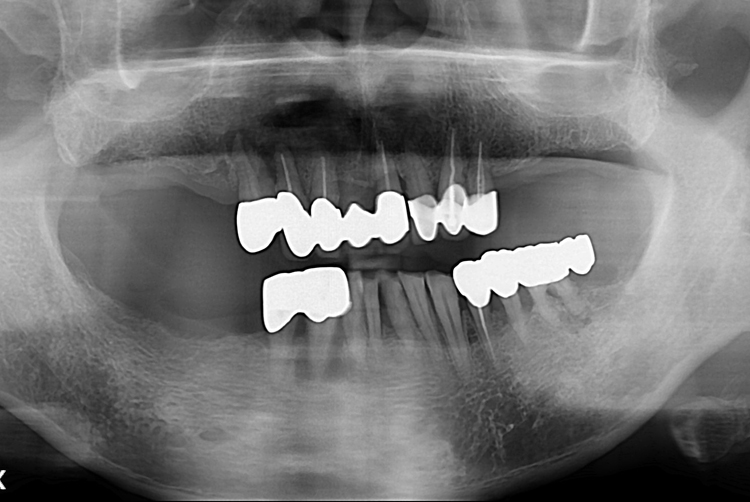

[임플란트] 전체 임플란트

치료전 : 2019-05-08